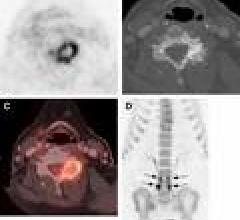

May 14, 2009 -On May 8, 2009, CMS opened the reconsideration of the National Coverage Determination (NCD) on Positron Emission Tomography (FDG). The requestors have asked CMS to reconsider the NCD and broaden national coverage of FDG-PET (without CED restrictions) for the staging of cervical cancer (i.e.